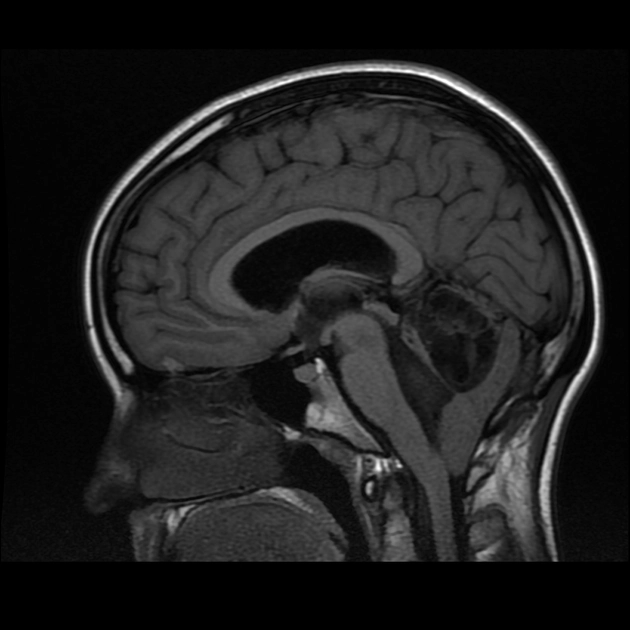

U sao bào lan tỏa (Diffuse Astrocytoma)